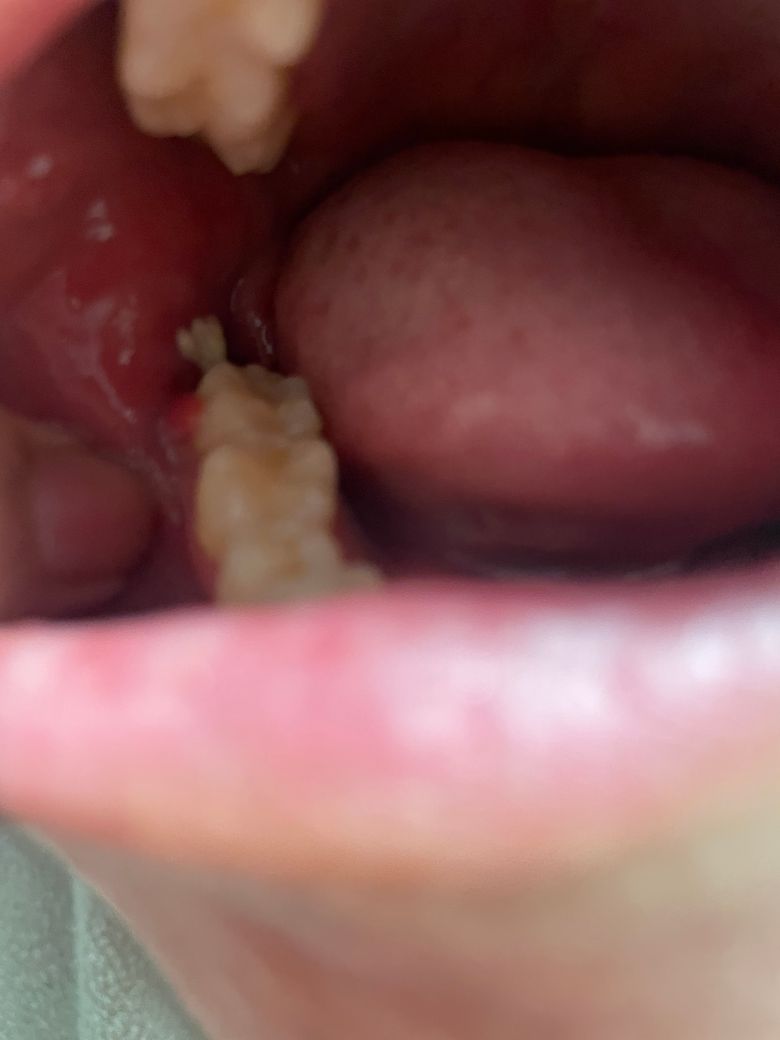

사랑니 뽑은지 2주가 되어가는데요. 사진 속 하얀 말랑한게 가글하면 튀어나옵니다. 근데 떨어지진 않고 끝에 조금 붙어있어서 더 건드리진 않았어요. 냅두면 사랑니 뽑고 난 구멍 안쪽으로 쏙 들어가더라구요. 떨어지지 않는거 보면 음식물은 아니고 낫고 있는 과정 인건가요? 그리고 앞에 빨간 살? 같은 것도 이상있는 건 아닌지 궁금합니다

사랑니 뽑은 자리 가장자리에 하얗게 딱지 앉은 것으로 보면 됩니다. 그냥두면 저절로 없어집니다. 잇몸 가장자리가 아물고 있는 것으로 보면 됩니다.

발치부위 치유 과정 중의 염증육아조직으로 보입니다 그 앞 어금니 주위의 잇몸 발적은 치과가서 따로 체크해보시기 바랍니다